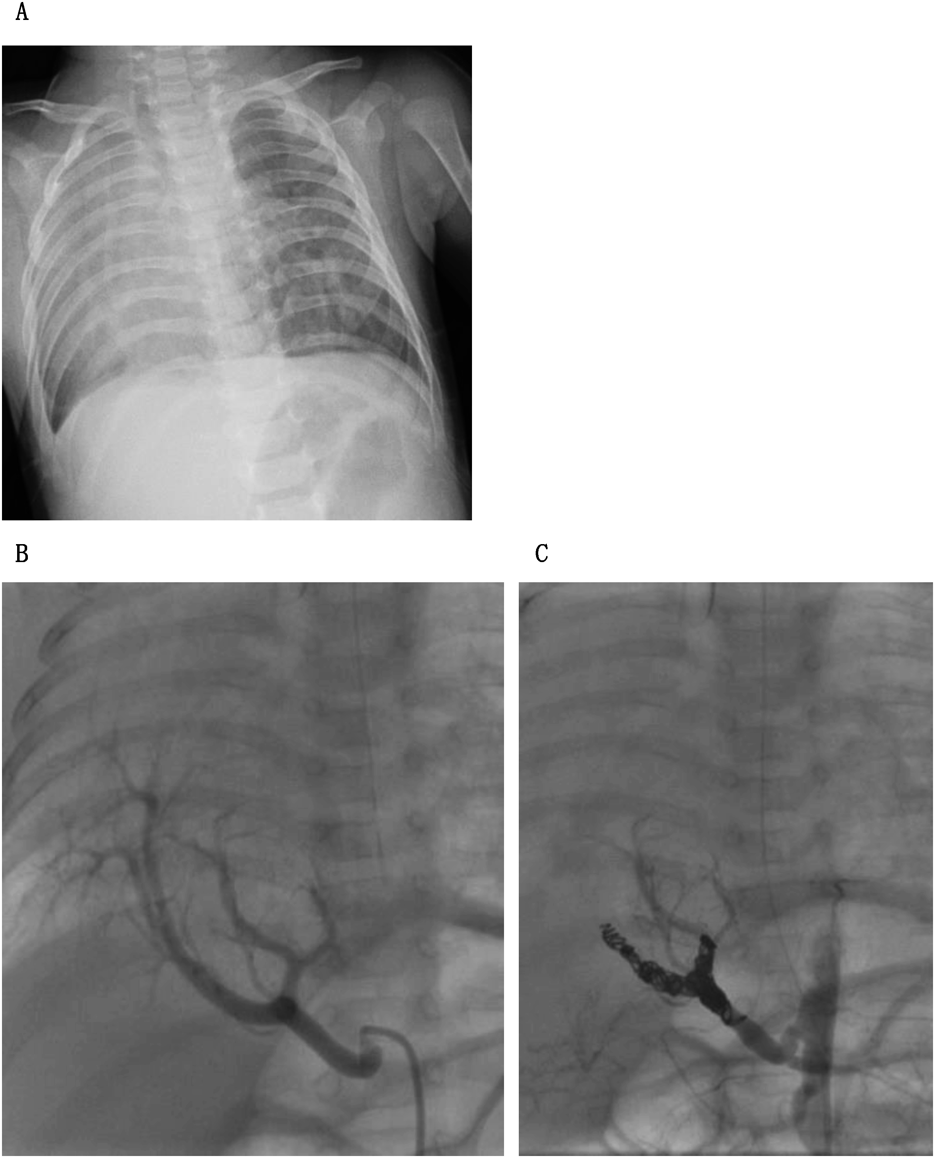

異なる生命予後を示したscimitar症候群の同胞例とリスク因子の検討Familial Scimitar Syndrome with Different Outcomes and Risk Factors